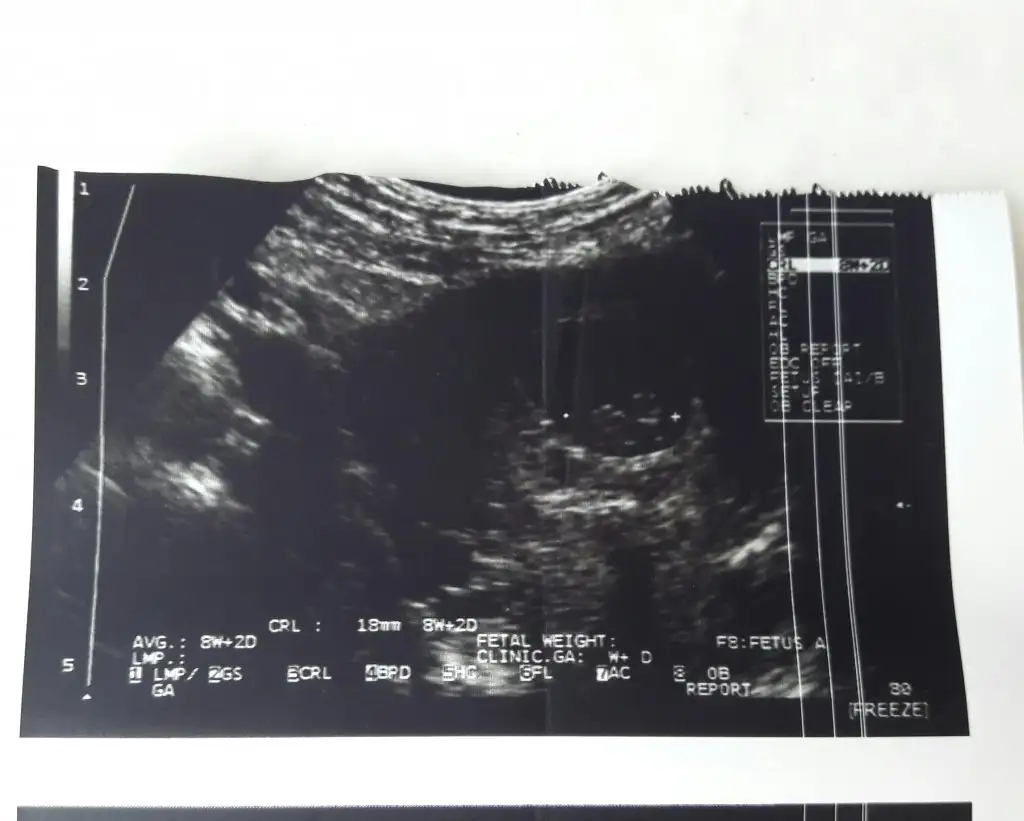

11 haftalık sizce ne ?Erkek gibi

Karından usg ise erkek vajinal bakıldıysa kızbana da bir yorum yapabilirmisiniz?Ikra meyra